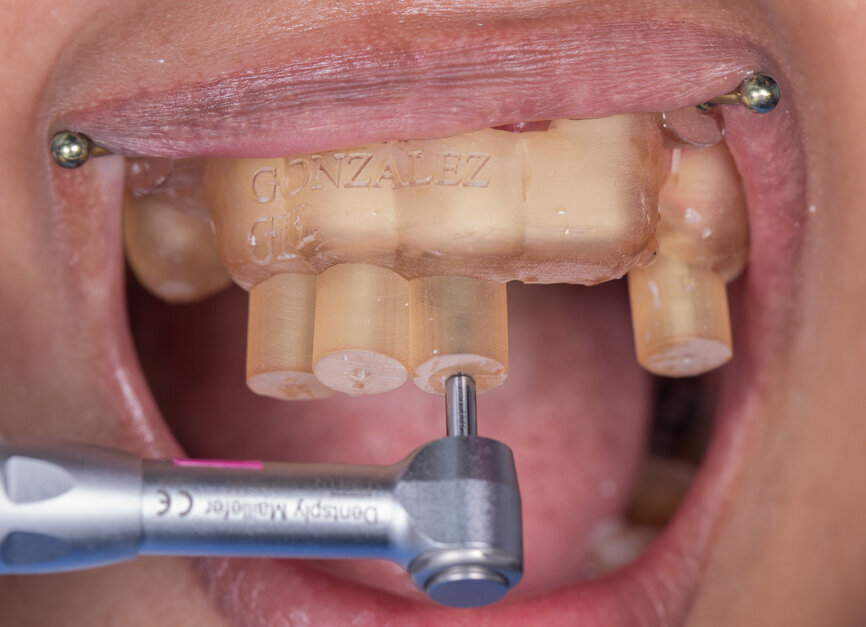

Fig. 1a: Static navigation stent used for endodontic access cavity preparations. The pre-planned stent does not allow for reorientation of the drill during the preparation. This can be consequential in accessing calcified, sclerosed canals. (Courtesy of Dr Paula Villa)

Fig. 1b: Three-dimensional stent printed for static navigation guidance to facilitate removal of an instrument in the periapex. Stents are cumbersome, bulky and restrictive in posterior regions. Once planned, the osteotomy path cannot be altered. (Courtesy of Dr Hugo Sousa Dias)